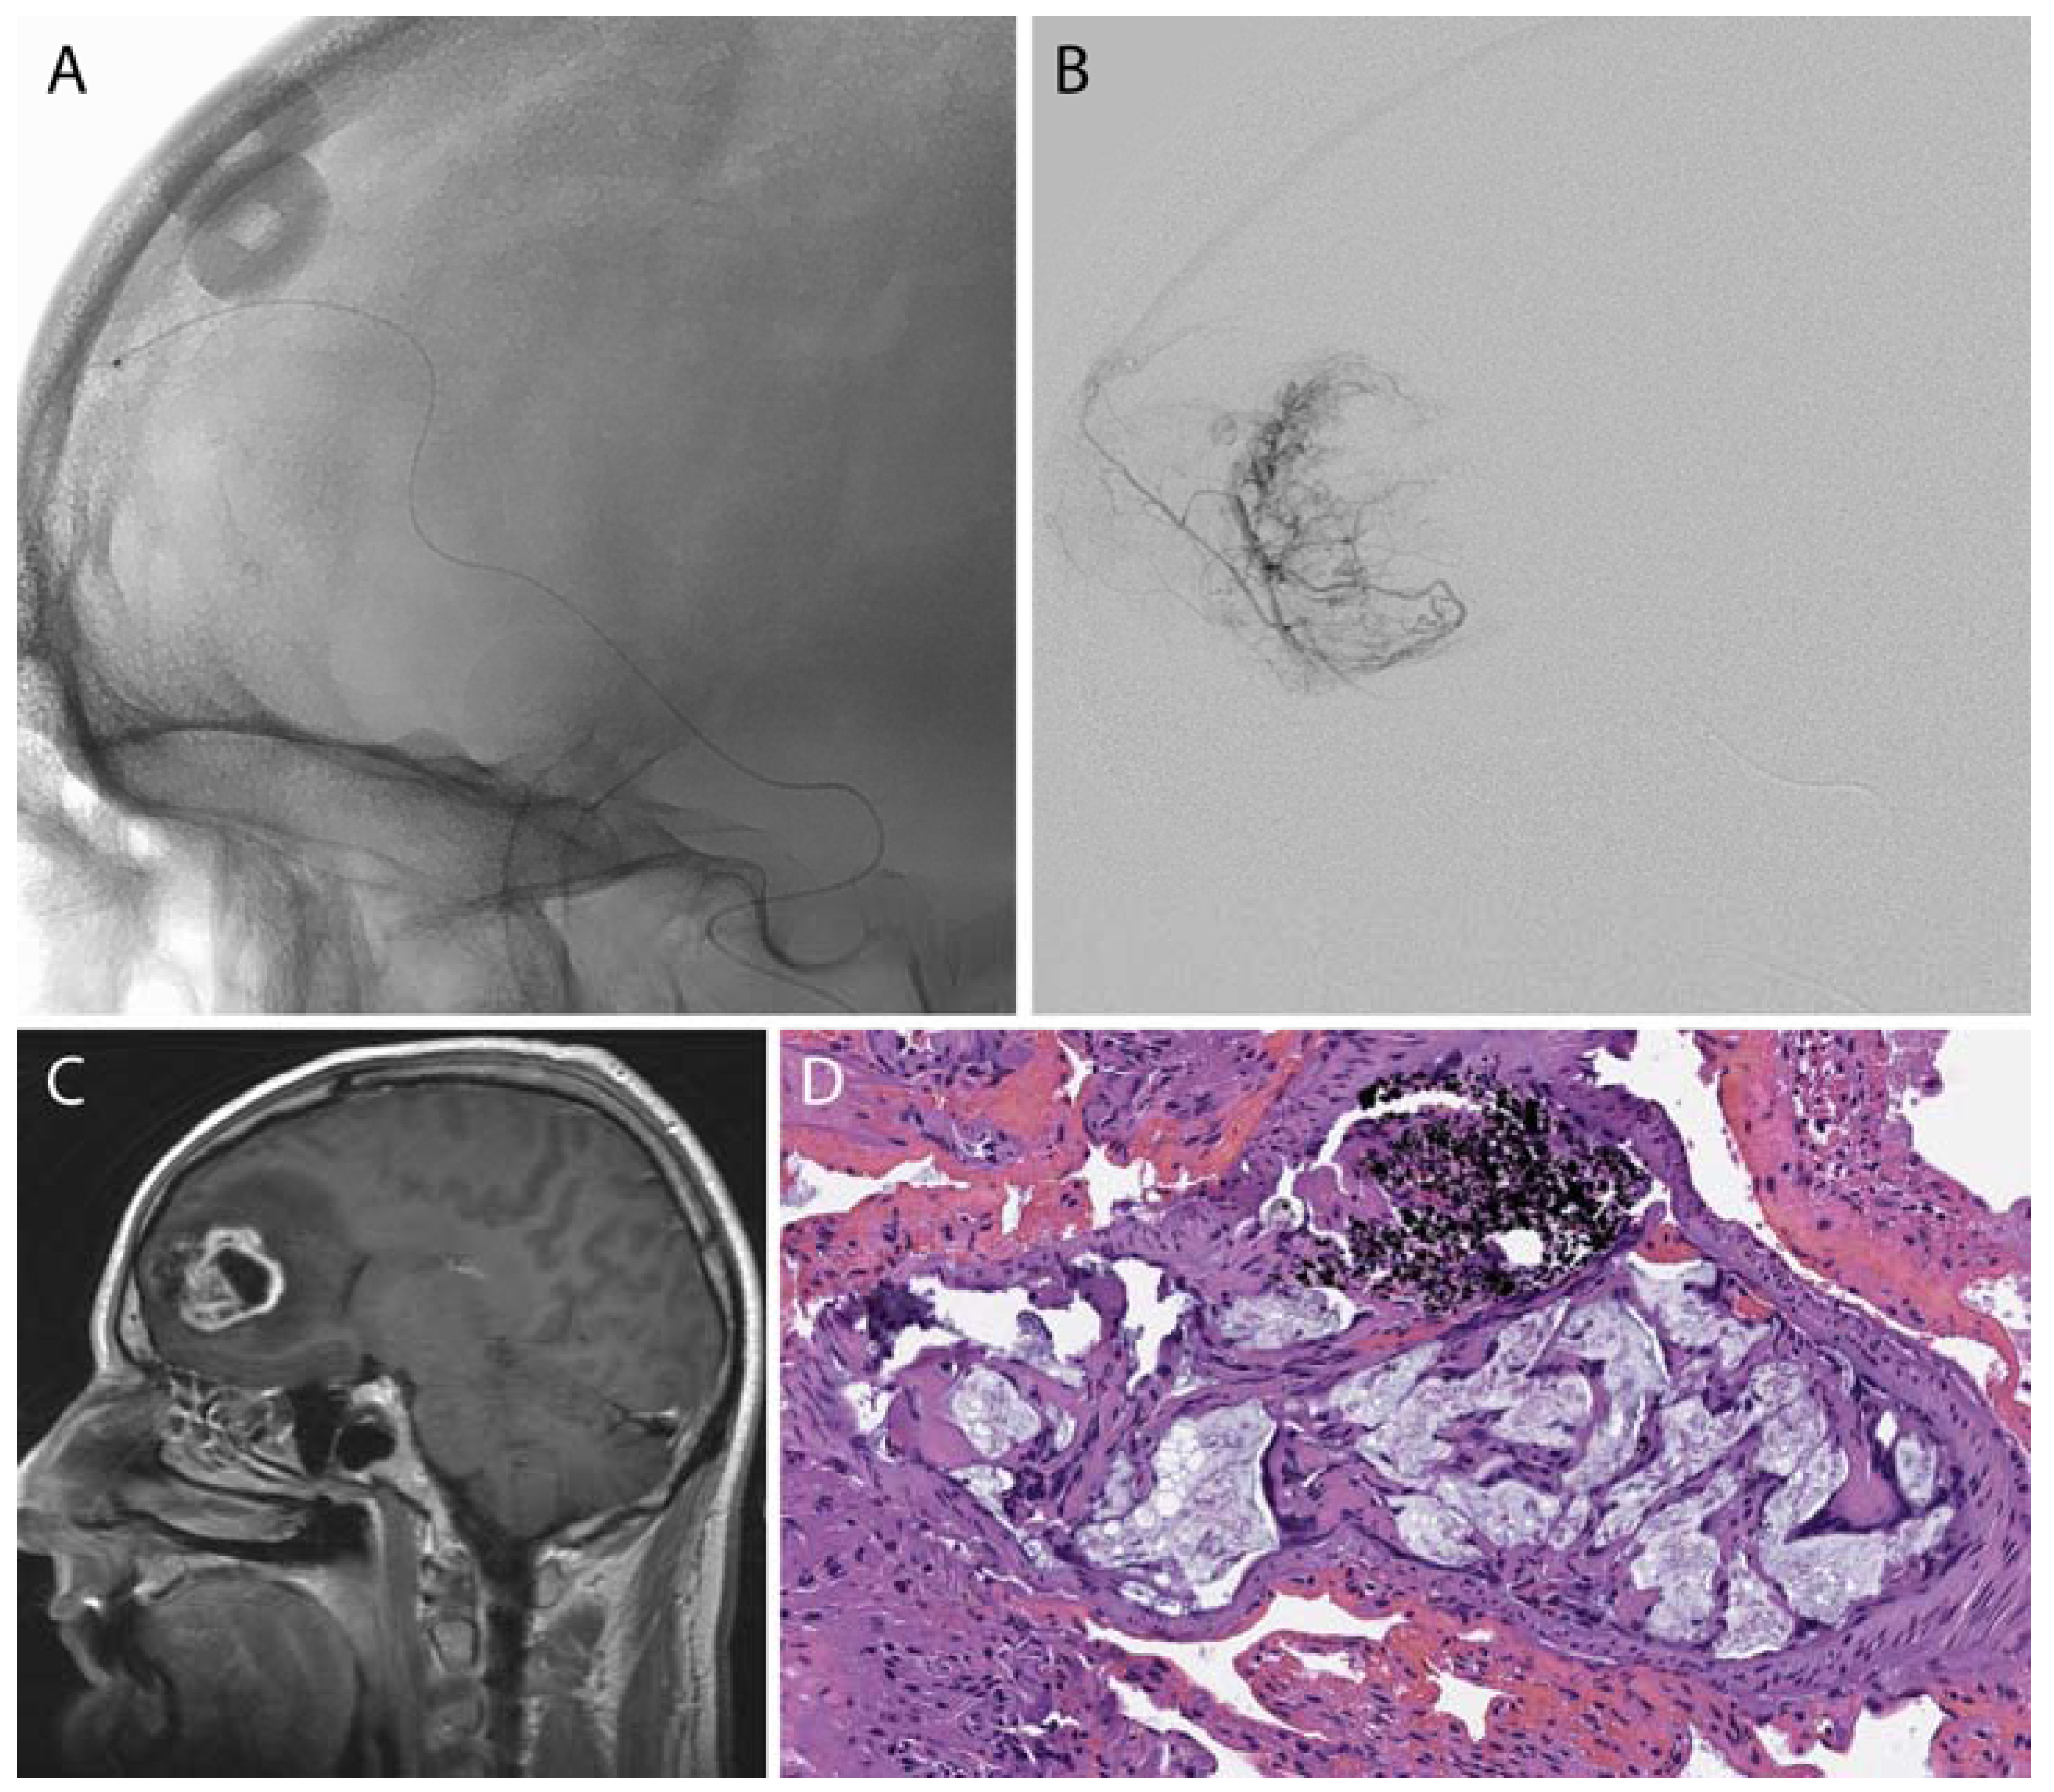

Figure 2.

A frontal lobe glioblastoma multiforme was pre-operatively embolized using polyvinyl alcohol (PVA) microspheres. A microcatheter (A,B) was advanced to a branch of the middle meningeal artery that supplied the tumor (C). (D) Post-surgical histology demonstrated PVA (acellular light blue mucoid material) within the tumoral blood vessels in the tumor comprised of pleomorphic large tumor cells; of note, the black material represents the “liquid embolic” agent Onyx (Medtronic-Covidien, Irvine, CA, USA).

Figure 3.

A falcine meningioma was pre-operatively embolized using PVA microspheres. A microcatheter (A,B) was advanced to a branch of the middle meningeal artery supplying the tumor (C). Post-surgical histology shows PVA microspheres within the tumoral tissue (D).